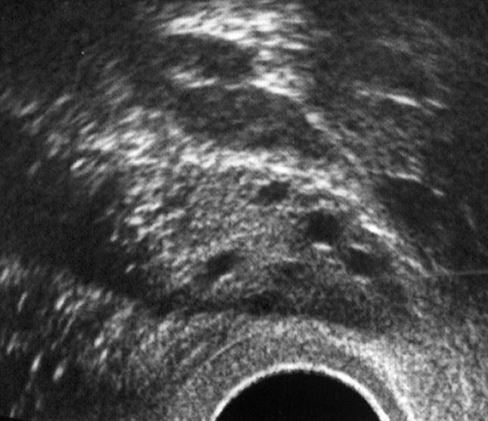

Hormonal stimülasyon öncesi

Hormonal stimülasyon sonrası